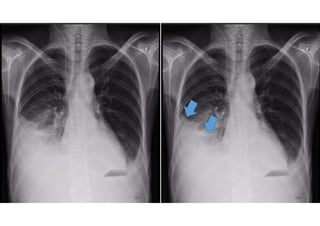

O QUE É?

 A tecnologia de Raio X funciona emitindo radiação que

atravessa o corpo e é captada por um detector ou

filme fotográfico.

 Os diferentes tecidos do corpo absorvem a radiação em

diferentes graus, criando uma imagem contrastante que

destaca ossos, órgãos e outras estruturas internas.

Tecidos densos, como ossos, aparecem brancos,

enquanto tecidos mais suaves, como músculos e

gordura, aparecem em tons de cinza.

DESVANTAGENS?

 A exposição à radiação, embora geralmente baixa,

pode acumular-se com exames repetidos,

aumentando o risco de efeitos adversos a longo prazo.

A radiografia também pode ser menos eficaz em

visualizar tecidos moles e em fornecer detalhes

comparáveis a outros métodos de imagem, como a

ressonância magnética (RM) ou a tomografia

computadorizada (TC).